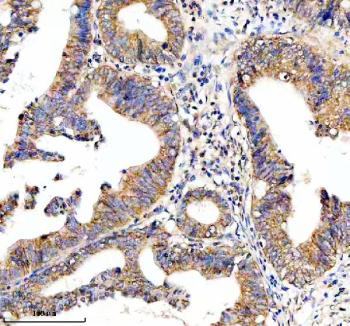

Immunohistochemical staining of HTR3E using anti-HTR3E antibody. HTR3E was detected in a paraffin-embedded section of human colon cancer tissue. Heat mediated antigen retrieval was performed in EDTA buffer (pH 8.0, epitope retrieval solution). The tissue section was blocked with 10% goat serum. The tissue section was then incubated with 2 ug/ml rabbit anti-HTR3E antibody overnight at 4oC. Peroxidase Conjugated Goat Anti-rabbit IgG was used as secondary antibody and incubated for 30 minutes at 37oC. The tissue section was developed using an HRP secondary and DAB substrate.